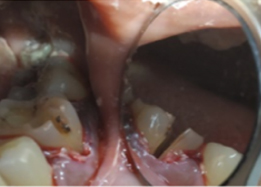

Bone Graft Placement

Placement of PRF Membrane